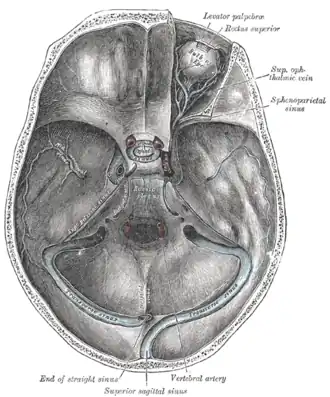

Base of the skull. Upper surface. Groove for transverse sinus labelled at bottom.

Base of the skull. Upper surface. Groove for transverse sinus labelled at bottom. -

Base of the skull. Upper surface. Transverse sinuses are drawn at bottom.

Base of the skull. Upper surface. Transverse sinuses are drawn at bottom.